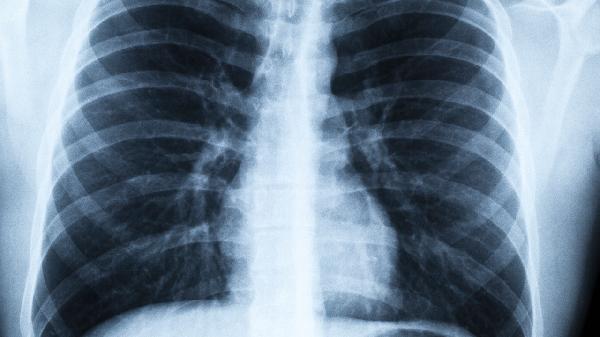

记住,戒烟的最佳时间永远是现在!无论你是30岁还是60岁,肺部都在等待这个重获新生的机会。那些戒烟10年的人,肺部CT显示的黑点会逐渐变淡,就像时光在慢慢擦拭吸烟留下的痕迹。别让"已经晚了"的念头,成为你与健康之间的最后一道屏障。